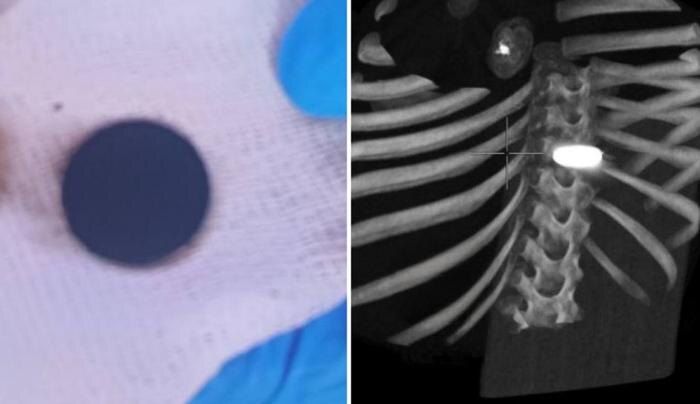

В Челябинске врачи сделали неожиданное открытие во время плановой операции на сердце четырёхлетней пациентки. Хирурги заметили в желудке девочки инородное тело, которое сначала приняли за опасную батарейку. Об этом сообщили в пресс-службе Центра сердечно-сосудистой хирургии.

Пациентку из Оренбурга госпитализировали для устранения врождённого порока сердца. В ходе вмешательства медики провели экстренную компьютерную томографию и обнаружили объект. Девочку срочно перевезли в другую больницу, где предмет извлекли.

Им оказалась крупная, сильно окислившаяся монета, которая, судя по её виду, пролежала в желудке не один день. При этом ребёнок не жаловался на боль. Как пояснила кардиолог Татьяна Дик, на стандартных рентгеновских снимках монета не была видна, поэтому её не обнаружили раньше.